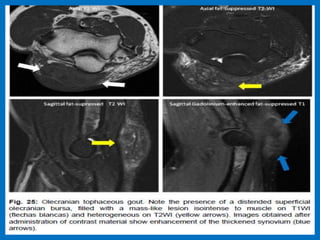

Avulsion of the distal triceps tendon (white arrow), with extensive overlying olecranon bursitis (black

arrows). There is cortical disruption (arrowhead) compatible with a small osseous avulsion.

Olecranon bursitis.